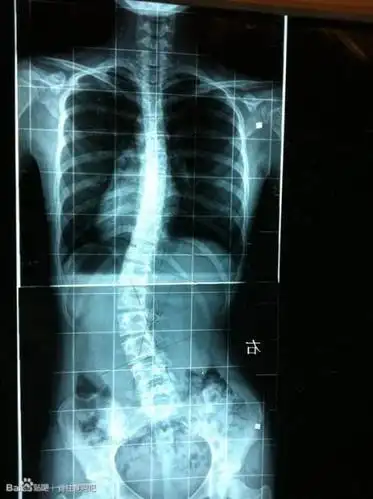

脊椎侧弯30度

两侧肩部不等高;脊柱侧弯早期有以下常见临床表现吉林大学中日联谊

脊柱侧弯典型病例